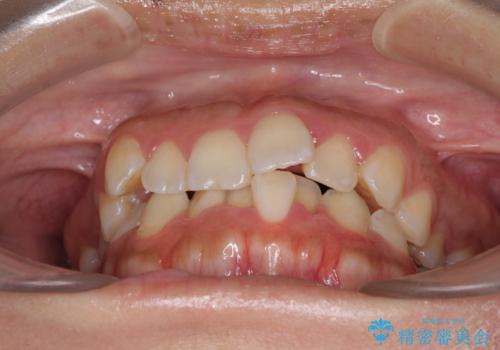

前歯のデコボコをインビザラインでスッキリと

- 上下前歯のデコボコを気にして来院された患者様です。

デコボコを解消する過程で、歯列の拡大により口元が突出する可能性があったため、4本の親知らずを抜歯しておき、歯列全体が後方に移動するように設計し、インビザラインにて矯正治療を行うこととしました。